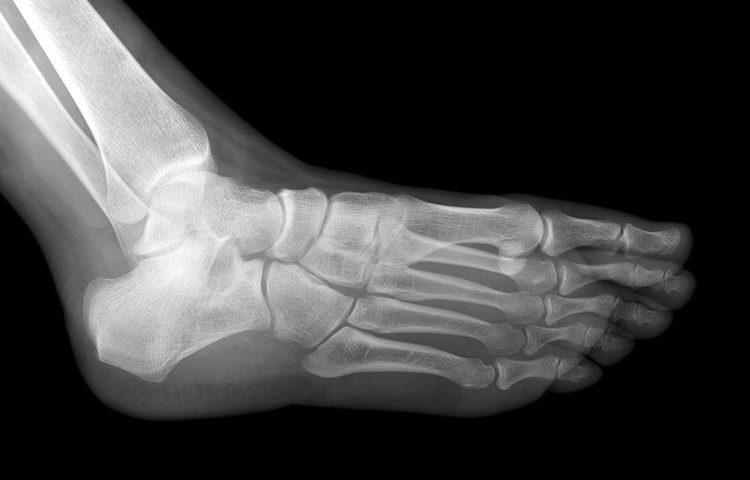

Το πέλμα είναι το μέρος του ποδιού που δέχεται τα πιο πολλά φορτία. Παράλληλα, δέχεται πιέσεις τόσο εσωτερικά από τα οστικά εξογκώματα, όπως το εξόγκωμα της πτέρνας και τις κεφαλές των μεταταρσίων, όσο και εξωτερικά από το έδαφος.

Από αυτά προστατεύεται με έναν ιστό λίπους και με ινώδη συνδετικό ιστό, που έχουν ρόλο συνεκτικό, μονωτικό και αντικραδασμικό, συγκρατώντας και καταμερίζοντας τα φορτία, καθώς προσφέρουν και μόνωση από το ψύχος και τη ζέστη.

Η πτέρνα και οι κεφαλές των μεταταρσίων δέχονται τις μεγαλύτερες πιέσεις και εκδηλώνουν τα περισσότερα προβλήματα.

Η πιο συχνή και επώδυνη πάθηση της πτέρνας είναι η άκανθα, φλεγμονή στην έκφυση της πελματιαίας απονεύρωσης της πτέρνας. Η πελματιαία απονεύρωση είναι μια παχειά, ινώδης ταινία, η οποία βρίσκεται κατά μήκος του πέλματος και εκτείνεται από τα φύματα της πτέρνας μέχρι τις κεφαλές των μεταταρσίων.

Λειτουργεί σαν πλατφόρμα η οποία σταθεροποιεί το πόδι και διατηρεί την ποδική καμάρα κατά τη φόρτιση. Η περιοχή αυτή δέχεται τις μεγαλύτερες πιέσεις στο έσω φύμα της πτέρνας. Ο όρος πελματιαία απονευρωσίτιδα υποδηλώνει μια χρόνια εκφυλιστική εξέλιξη η οποία δημιουργείται από επαναλαμβανόμενη υπέρμετρη φόρτιση. Γι΄ αυτό είναι συχνή στα υπέρβαρα άτομα, καθώς και σε αυτά που έχουν έντονη δραστηριότητα, όπως είναι οι αθλητές μεγάλων αποστάσεων και σε άτομα μέσης ηλικίας (η συχνότερη ηλικία εμφάνισης της νόσου).